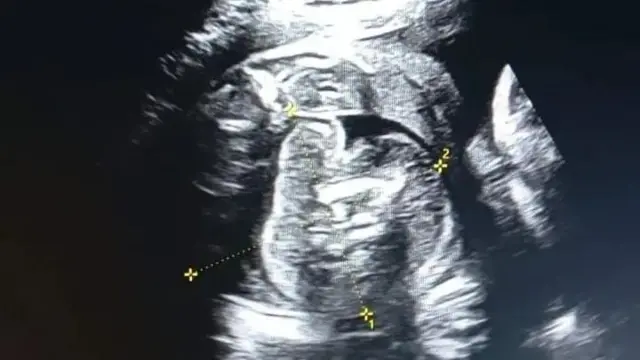

ভারতের মহারাষ্ট্রে একটি বিরল ঘটনা প্রকাশ্যে এসেছে। ওই রাজ্যে ৩২ বছর বয়সী এক নারীর গর্ভে থাকা শিশুর শরীরে আরও একটি ভ্রূণের সন্ধান পাওয়া গেছে।

ঘটনাটি মহারাষ্ট্রের বুলধানা জেলার। সেখানকার একটি সরকারি হাসপাতালে ওই গর্ভবতী নারী সোনোগ্রাফি করানোর জন্য আসেন। তখনই এই ঘটনা লক্ষ্য করেন চিকিৎসকেরা।

বুলধানা জেলায় ৩২ বছরের ওই নারী তার গর্ভাবস্থার অষ্টম মাসে সোনোগ্রাফি করাতে সরকারি হাসপাতালে এসেছিলেন।

সেই সময় পরীক্ষা করে জানা যায়, ওই নারীর গর্ভে যেমন একটি শিশু রয়েছে, তেমনই ওই শিশুর গর্ভেও একটি ভ্রূণ রয়েছে। বিষয়টি সম্পর্কে নিশ্চিত হতে চিকিৎসক এবং বিশেষজ্ঞদের একটি টিম আরও একবার সোনোগ্রাফি করেন।

তখনও গর্ভে থাকা শিশুটির গর্ভে একটি ভ্রূণ স্পষ্টভাবে দেখা যাচ্ছিল।